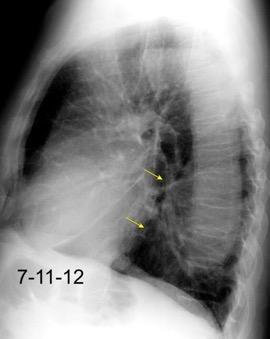

Tromboembolismo pulmonar Diafragma elevado 20%

Consolidación por Infarto pulmonar. (TEP)